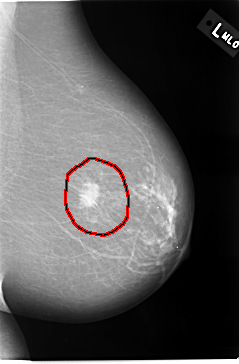

C_0037_1.LEFT_MLO

FILE: C_0037_1.LEFT_CC.OVERLAY

TOTAL_ABNORMALITIES 1

ABNORMALITY 1

LESION_TYPE MASS SHAPE IRREGULAR MARGINS ILL_DEFINED

ASSESSMENT 5

SUBTLETY 5

PATHOLOGY MALIGNANT

TOTAL_OUTLINES 1

BOUNDARY